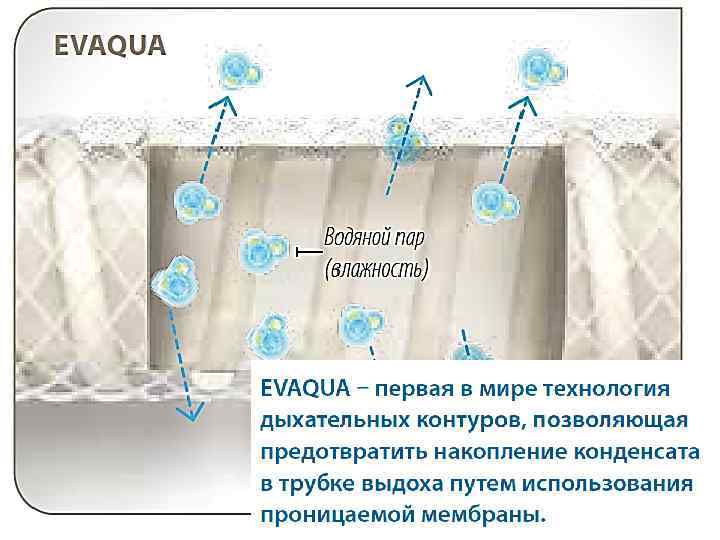

В шлангах тэн

В шлангах тэн

Тен под держ в конт уре защи ивает тем щае тера т от туру конд и енса ции

Тен под держ в конт уре защи ивает тем щае тера т от туру конд и енса ции